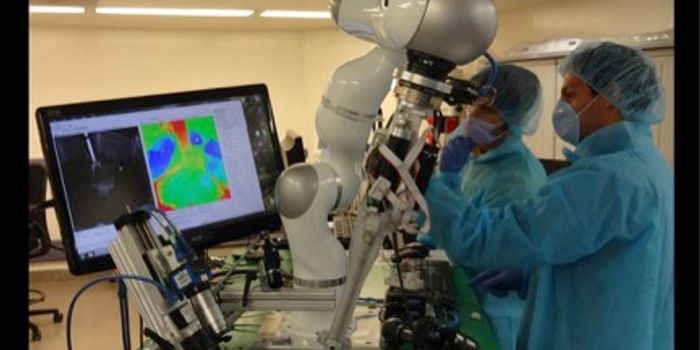

OCT 07, 2021Cell & Molecular BiologyWhen cancer is diagnosed, a sample has to be taken from a patient, treated, and analyzed. Researchers have now modified ...

DEC 03, 2020NeuroscienceTo obtain high-resolution images of the brain, researchers usually need to reduce the thickness of the skull or cut into ...

MAY 14, 2021MicrobiologyResearchers have created an imaging agent that will allow scientists and clinicians to visualize a bacterial infection c ...

AUG 12, 2021Clinical & Molecular DXResearchers have developed a new technology for the non-invasive diagnosis of thyroid cancer that combines photoacoustic ...

APR 21, 2020Clinical & Molecular DXResearchers have developed a handheld device that can image structures under the skin at resolutions 100 times greater t ...